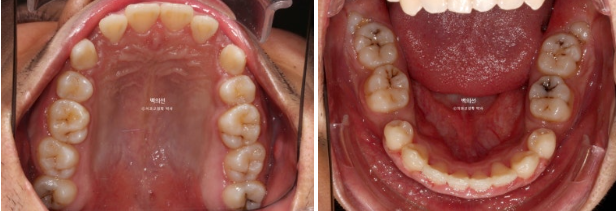

앞니를 위로 올려 뼛속 방향의 이동인 함입을 도모하게 되면 잇몸도 치아와 함께 올라가며 웃을 때 잇몸노출량이 줄어듭니다.

이를 위해 교정용 나사가 필요합니다.

치료시작 1년 차 과개교합은 해소가 되었습니다.

앞니 각도와 어금니 교합은 좋고 1급 교합관계를 보입니다.

초진에 비해 치근흡수는 없고 치근평행도도 좋습니다.